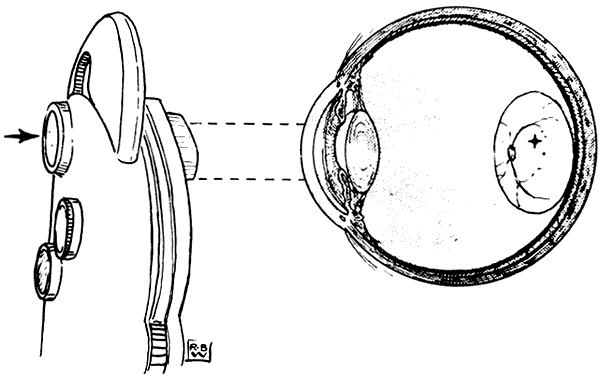

Less marked and relatively steady eccentricity of fixation (a few degrees or less of visual angle) is common and can be detected by the clinician with various tests. Visuscopic devices (no longer available as separate instruments, but simulated by some direct ophthalmoscopes that provide a selection of viewing apertures) project directly onto the retina an image of a target or a small object that can be fixated by the patient (Fig. 11). By comparing the position of this image with that of the foveolar light reflex, the examiner can estimate the degree of eccentric fixation.

Fig. 11. The Visuscope. (Von Noorden GK, Maumanee AE. Atlas of Strabismus. 2nd ed. St Louis: CV Mosby, 1973:81.)

The entoptic phenomenon of Haidinger brushes, seen best when a blue field is viewed through a rotating polarizing filter (available as an accessory with most synoptophores), allows the patient to identify subjectively the visual direction of the foveola. This corresponds to the apparent axis of rotation of a wispy spinning image that resembles a bowtie, butterfly, or airplane propeller shifting position with each fixation movement of the eye. Angular separation of this point from the fixation point can be determined with the aid of a superimposed figure (traditionally a frontal view of an airplanein relation to which the propeller is located whenthe nose is visually fixated). Both visuscopy andHaidinger brush assessment of eccentric fixation require a patient who is fully cooperative, and even then it may be difficult to obtain reliable information.